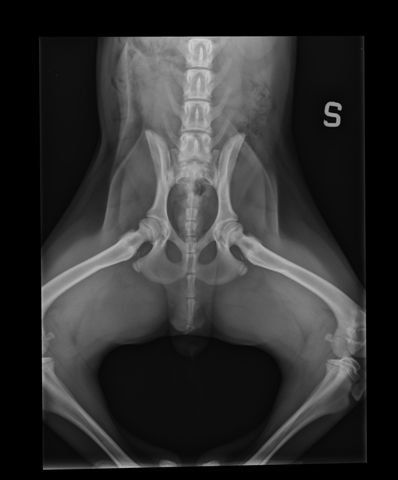

La displasia dell’anca è una malformazione articolare che si sviluppa durante la crescita del cane. Consiste in un errato accoppiamento tra testa del femore e acetabolo, che causa instabilità articolare, dolore e progressiva degenerazione della cartilagine.

Presso la nostra clinica, la prevenzione della displasia delle anche inizia con uno studio radiografico approfondito, effettuato in anestesia o sedazione controllata. L’esame è sicuro e permette di valutare l’articolazione anche nei cuccioli, già a partire dai 3 mesi e mezzo di età.

- radiografie in più proiezioni (standard, distratta, a rana e DAR);

- valutazione della colonna e, se necessario, anche dei gomiti.